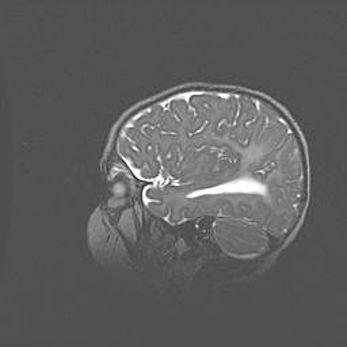

Аномалия Денди-Уокера. Признаки гипоплазии мозолистого тела.

Возраст: 5 месяцев 3 дня

Вес: 5550 г

Пол: мужской

Окружность головы: 39 см

Срок гестации: 40 недель

Аномалия Денди-Уокера – это порок развития головного мозга, для которого характерна триада симптомов: гипотрофия или аплазия червя мозжечка и/или полушарий мозжечка, расширение четвёртого желудочка с формированием ликворной кисты задней черепной ямки, гипертензионная гидроцефалия различной степени.

Гипоплазия мозолистого тела относится к дефектам внутриутробного этапа развития мозговой ткани, возникающим в процессе закладки структур головного мозга, что происходит на начальных этапах развития эмбриона.